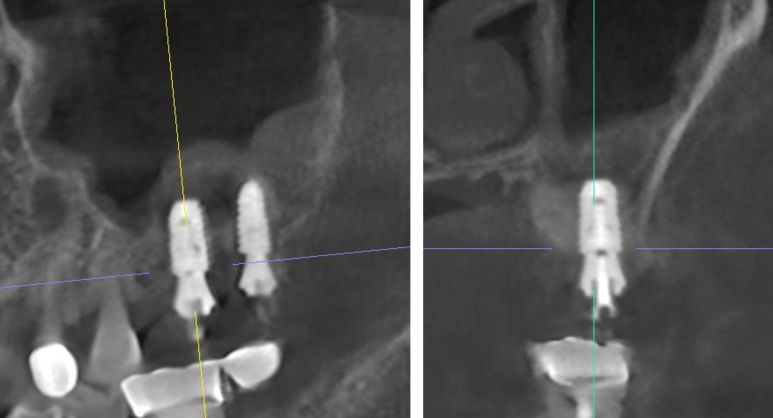

📸 수술 3개월 후 예후

- CT 상 점막 상태 양호

- 이식한 골 형성도 안정적으로 진행

- ISQ 수치(고정력 지표)도 정상 수치 도달

→ 예후가 매우 좋았습니다 😊